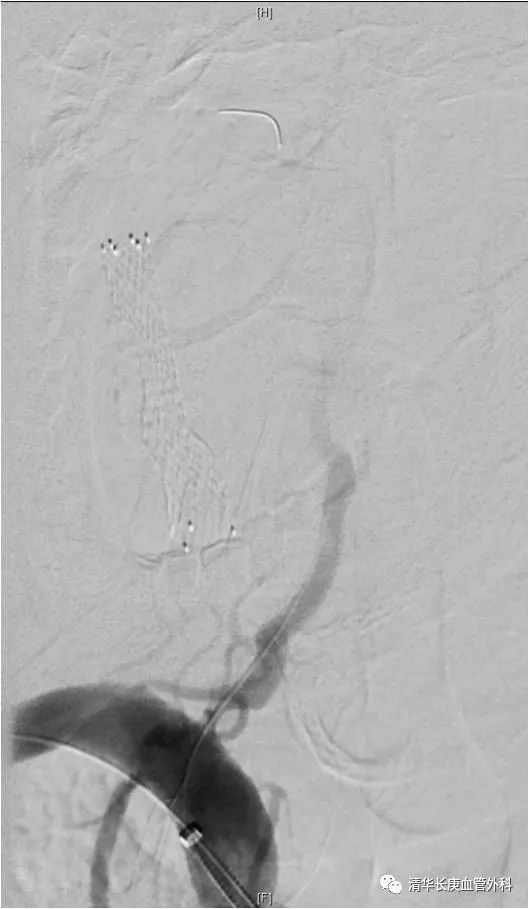

实战手术最具魅力,吴巍巍主任主刀演示胸腹主动脉瘤近端“原位开窗”、远端“改序”释放腔内修复术,将一例以往开胸开腹体外循环都难以修复的主动脉瘤“大”手术巧妙地转化为仅需要三个穿刺点的微创“小”手术,原位开窗精准利落,改序释放巧妙稳固,赢得了在场学员的称赞。